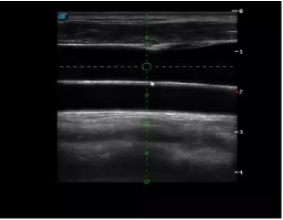

實(shí)時(shí)觀察穿刺針進(jìn)入血管的全過(guò)程,方便操作及較短的穿刺路徑,智能進(jìn)針尺寸提示,讓置管工作更加輕松,高效。

不同進(jìn)針路徑